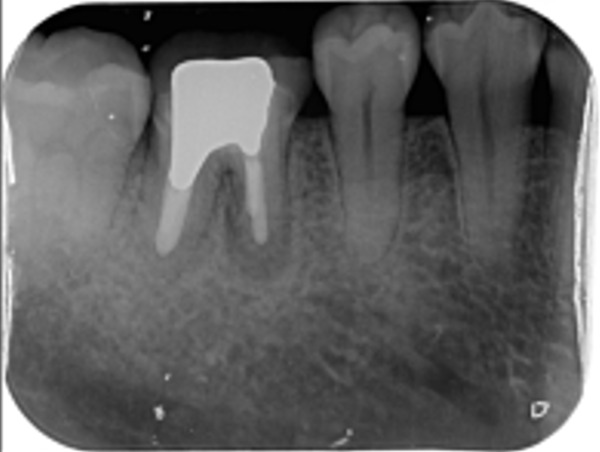

治療前のレントゲン写真は、こちらです。